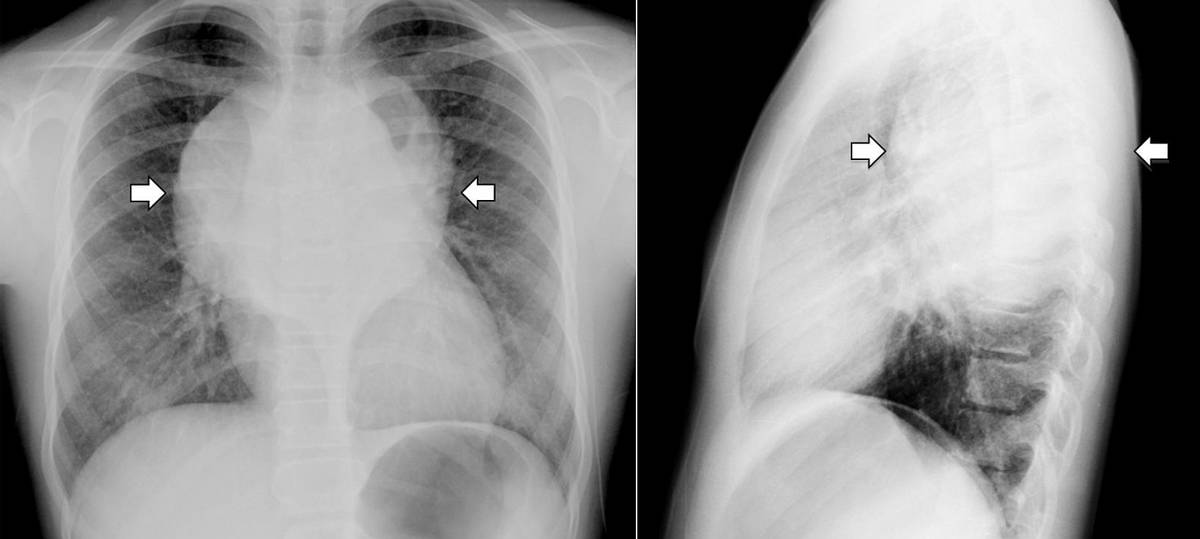

A 10-year-old girl with no significant past medical history was referred to our institution with a two-month history of posterior thoracic pain, which was aggravated by coughing and accompanied by anorexia, weight loss and cachexia. Physical examination and laboratory tests were unremarkable.

What could be the diagnosis ?